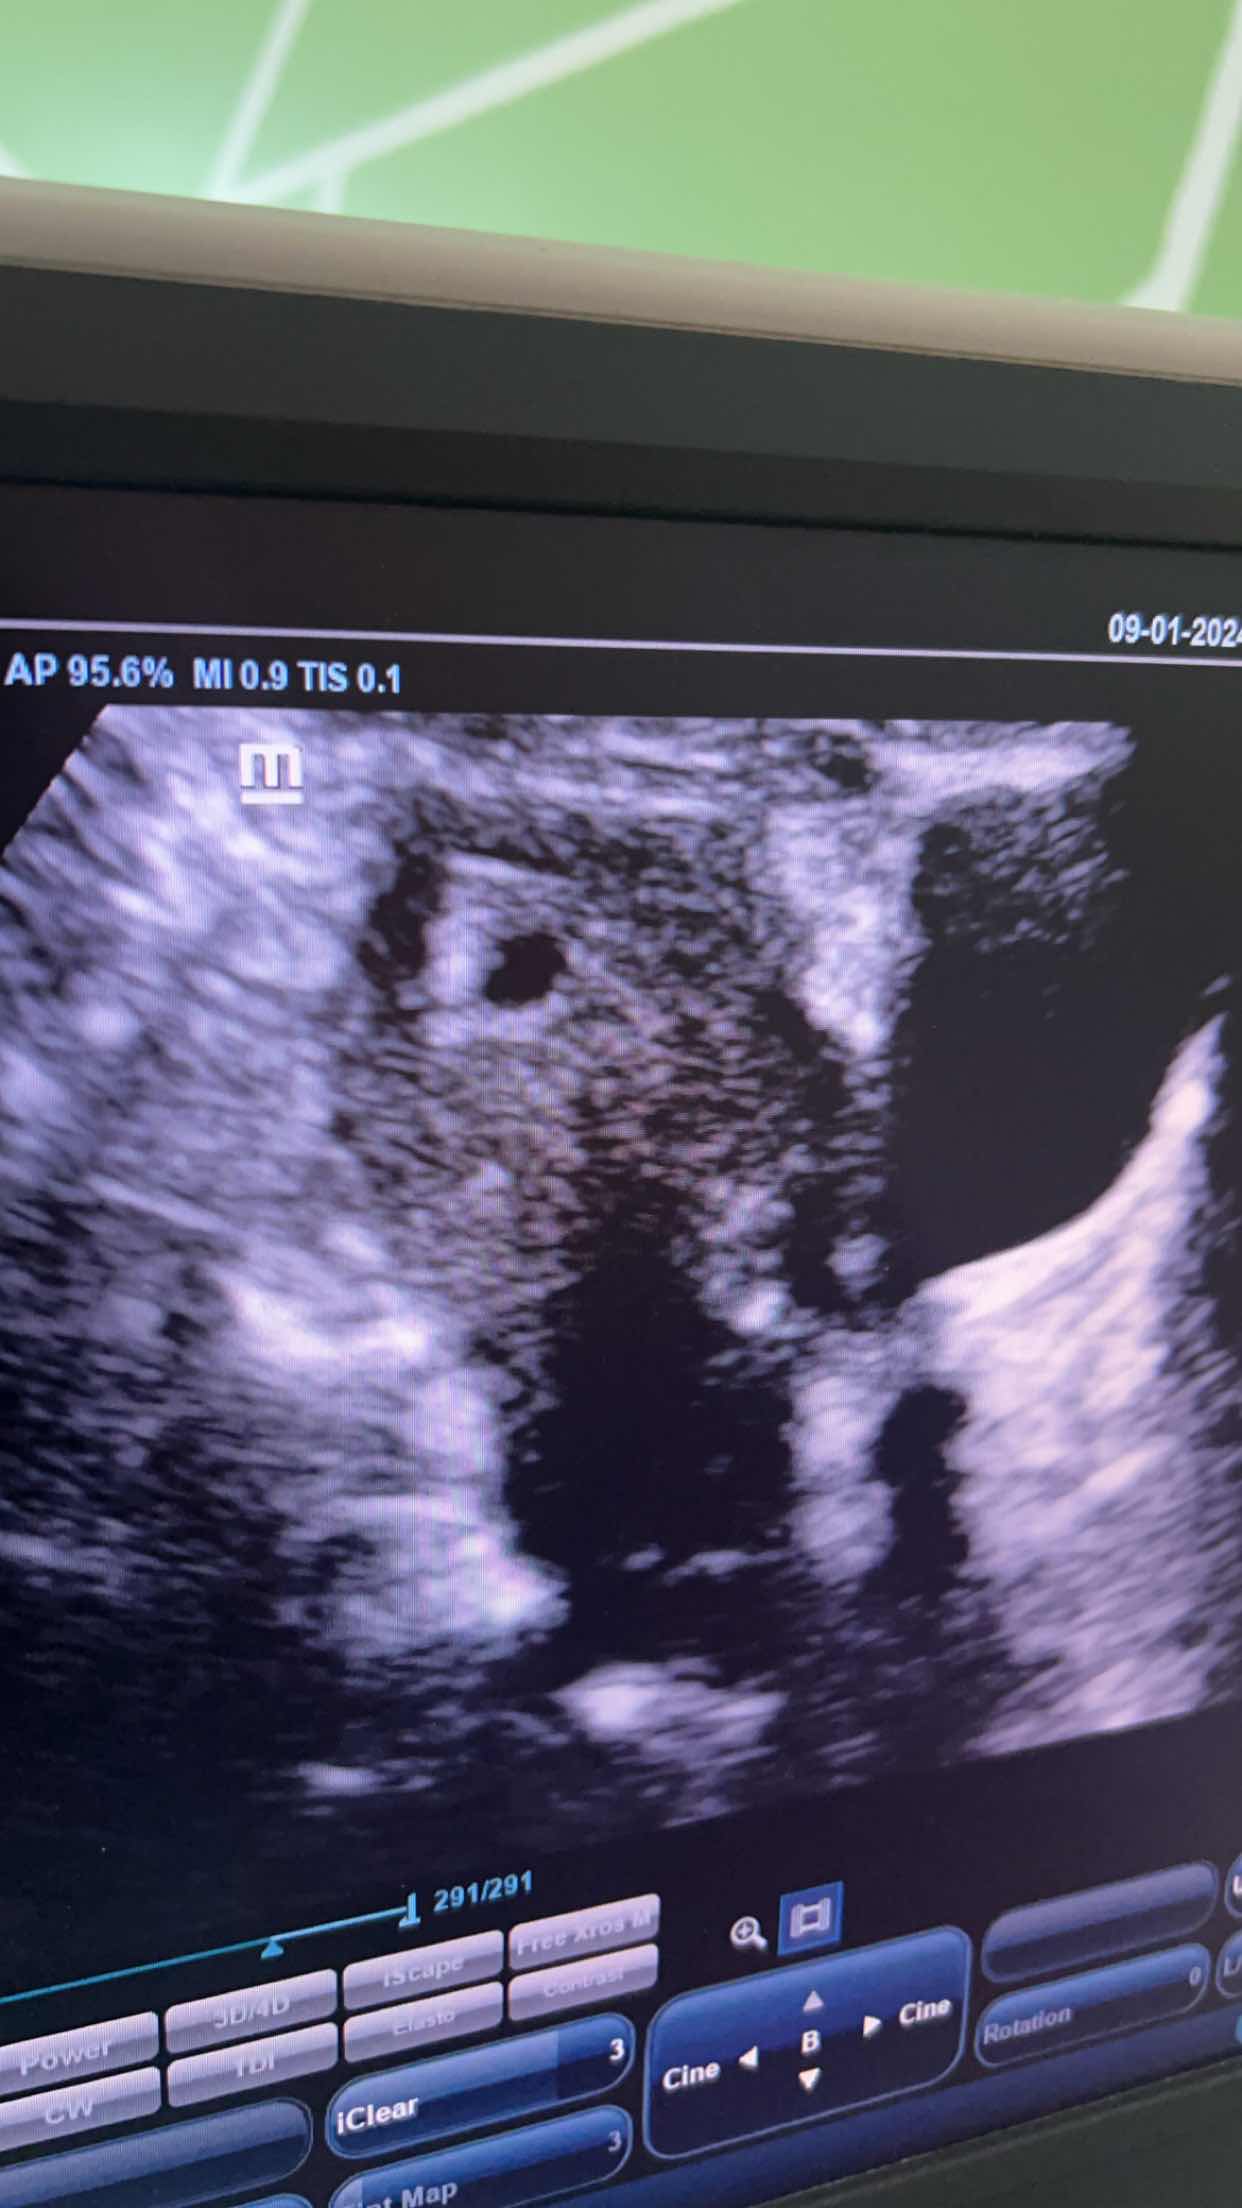

حامل ف الشهر الاول ولدي نزيف مهبلي